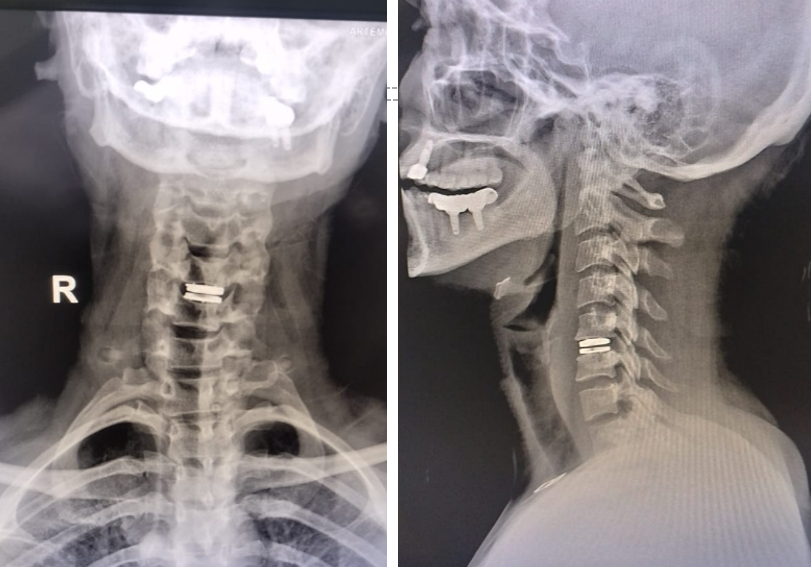

A surgery where a damaged spinal disc is removed and replaced with an artificial one that allows normal spine movement.

Through a small incision in the neck or abdomen, the damaged disc is removed.

Artificial Disc Placement

The damaged disc is replaced with an artificial disc to maintain spine movement.